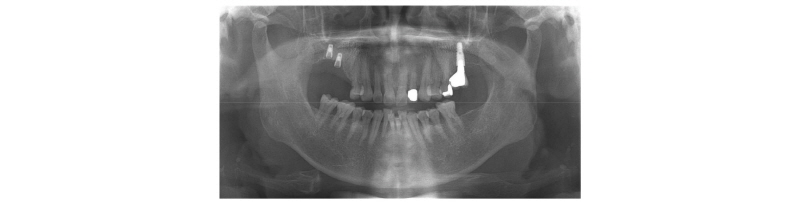

만 70세 남자 환자가 #16, #17 임플란트 파절 원인으로 임플란트 제거 및 임플란트 재식립을 위해 의뢰되었다. #15도 함께 상실되어 있었고, #25는 수직 파절되어 있었다(Fig. 1). 이전 환자 차트 기록을 살펴보았을 때, 2008년 본원에서 임플란트 수복을 한 기록이 있었다. 그 당시에도 좌측 하악 제2대구치가 상실되어 있었고, 이로 인해 우측으로 저작을 주로 하여 우측 임플란트에 피로 파절이 생긴 것으로 판단하였다. 실제로 문진 결과 왼쪽보다는 오른쪽으로 주로 저작한다고 하였다. Implant-crown ratio 가 불리하더라도 임플란트의 장기 생존률에는 큰 영향을 미치지 않는다는 연구 결과도 있지만, 현재 환자가 저작을 우측으로 한다는 점을 고려해서 좀 더 개선된 implant-crown ratio를 만들어주기 위해 수직적 골증대술을 시행하기로 하였다.